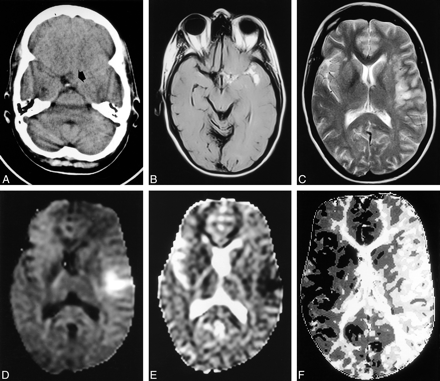

Images in patient 26, who presented 8 d after SAH.

A, CT scan shows a subtle finding of isoattenuating material (arrow) in the suprasellar cistern.

B, Axial fluid-attenuated inversion recovery (6000/96/1800) MR image shows extensive SAH as areas of high signal intensity in the suprasellar cistern and left sylvian fissure.

C, T2-weighted (3096/80 [TR/TE]) MR image shows areas of abnormal high signal intensity around the left insular cortex.

D, Diffusion-weighted MR image shows areas of high signal intensity due to infarction.

E, ADC map also shows that this finding is due to infarction.

F, Time-to-peak map from the perfusion-weighted MR sequence shows reduced perfusion in the entire left hemisphere.